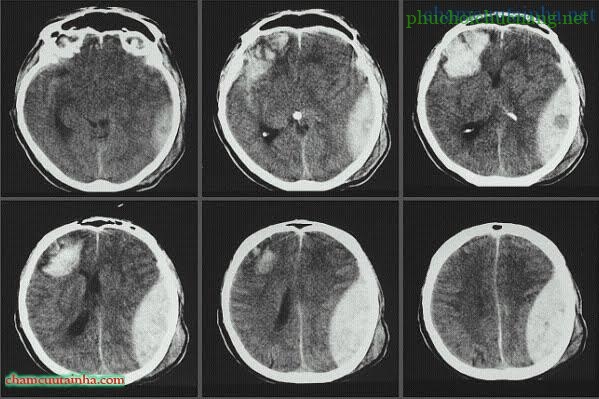

– CT-scan sọ não hoặc MRI sọ nãocho phép xác định được vị trí não bị tổn thương, loại tổn thương nguyên phát, thứ phát và mức độ nặng của tổn thương.

– CT-scan sọ não: hình ảnh các thương tổn nguyên phát và thứ phát của não do chấn thương.